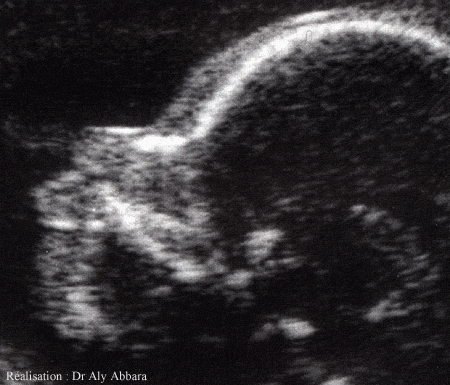

Coupe sagittale de la face montrant l'os propre du nez

Grossesse de 24 semaines d'aménorrhée